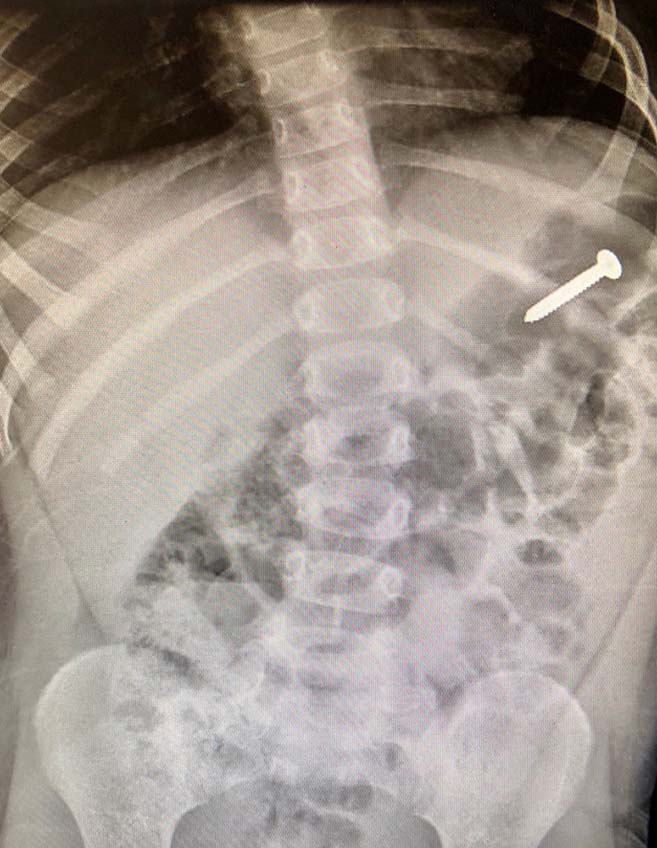

Radiografía o tomografía computarizada del objeto retenido.

Los eventos centinela, como las cirugías en el sitio equivocado y los objetos olvidados, definidos por la Comisión Conjunta como incidentes que causan la muerte, daños permanentes o daños temporales graves, desencadenan investigaciones obligatorias y análisis de las causas fundamentales. Estos ‘eventos que nunca deberían ocurrir’ (por ejemplo, esponjas o instrumentos olvidados dentro de los pacientes) nunca deberían ocurrir si se siguen los protocolos adecuados, pero provocan infecciones, dolor crónico o reoperaciones. Los abogados especializados en responsabilidad médica investigan a través de registros quirúrgicos, imágenes y testimonios para demostrar que la negligencia del equipo causó la lesión.